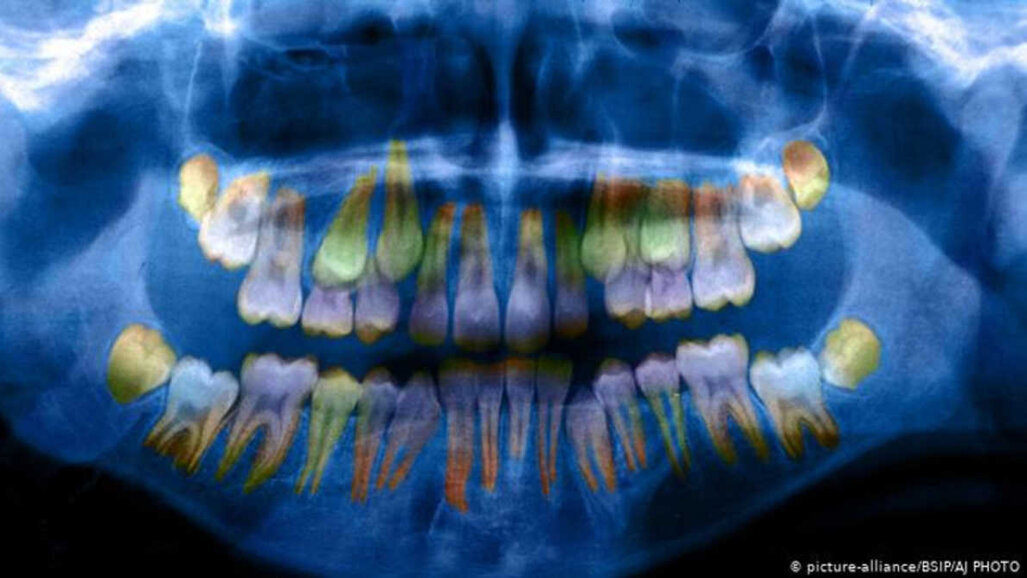

Nejdůležitějším zjištěním bylo, že na dětských zubech lze pozorovat, zda byly v raném věku vystaveny vysokým stresovým faktorům. Podle Dr. W. Thomase Boyce, profesora pediatrie a dětské psychiatrie na Kalifornské univerzitě v San Franciscu, který přednášel na setkání AAAS, jsou jednotlivé vrstvy, které vytvářejí zubní sklovinu, tenčí a méně husté, jsou-li vystaveny stresu, což „zvyšuje náchylnost k tvorbě zubního kazu“, jak vysvětlil německé mezinárodní televizní společnosti Deutsche Welle. Tyto změny lze měřit zkoumáním mléčného zubu v trojrozměrném modelu vytvořeném na základě na rentgenových snímků.

„Samozřejmě to, co ve skutečnosti chceme najít a co hledáme, avšak tyto snímky to nedokážou ukázat, je celková expozice kortizolu," dodal Boyce. Proto teprve zkoumání skutečných zubů může odhalit, jakým způsobem ovlivňuje tento stresový hormon jejich vývoj.